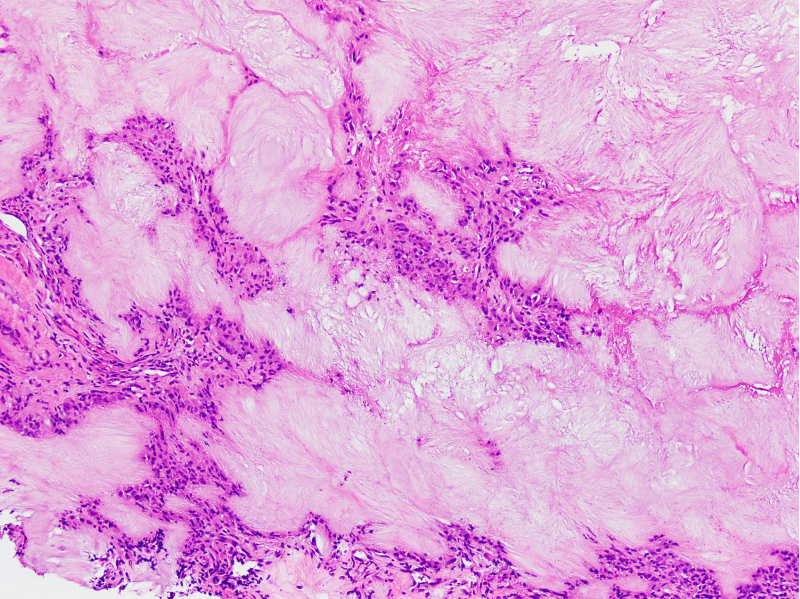

Microscopic (histologic) description

- Bone and cartilage changes:

- MSU crystal deposition in bone is associated with cystic erosion, secondary cortical fracture, destruction of bony trabeculae, osteonecrosis and infiltration of trabecular spaces by chronic inflammatory cells

- Other changes include fibrotic bone marrow with proliferation of dilated capillaries, osteoclastic and osteoblastic activity and new bone formation (BMC Musculoskelet Disord 2019;20:140)

- Affected cartilage appears fibrillated, eroded and fissured

- Granulation tissue formation, fibrous replacement and chondronecrosis may occur (BMC Musculoskelet Disord 2019;20:140)

Microscopic (histologic) images